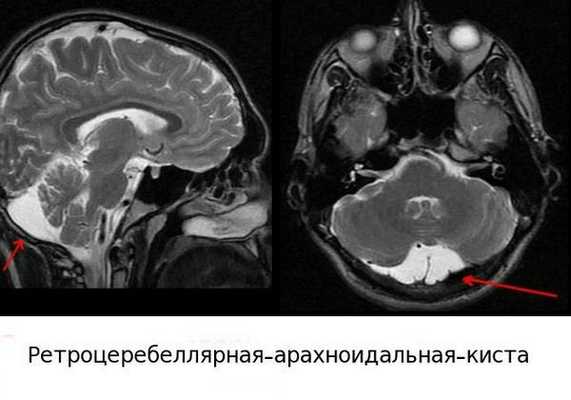

- При аномалиях развития мозжечка, таких как гипоплазия полушарий мозжечка (уменьшение его в размерах) или ретроцеребеллярная киста (новообразование в задней черепной ямке за мозжечком), ребёнок произносит слова тихим голосом по слогам. Это вызвано слабой воздушной струёй и происходит потому что киста сдавливает мозжечок и нарушает его работу.